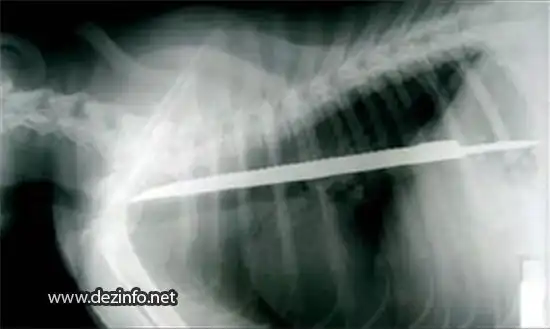

Детскую стрелу длиной в 25см проглатила собачка Бетти. Длинна самой Бетти всего 30 см.

30-ти сантиметровый зазубреный нож проглотил 6 месячный щенок бультерьера. Не понятно как, но собака не пострадала.